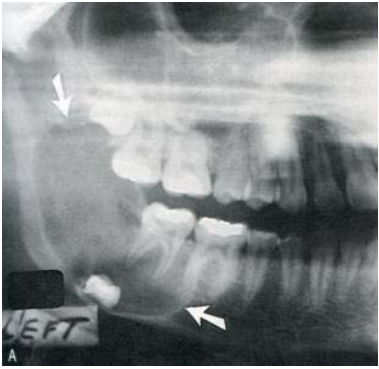

78.一位22歲男性患者之環口X光顯示兩側下顎臼齒下方有周界清晰之放射線透性(radiolucent)影像(圖A如箭頭標示),兩側上顎竇 亦有放射線不透性(radiopaque)影像,手術發現此病變為齒源性角化囊腫(odontogenic keratocysts);進一步檢查發現中面部 有一潰瘍病變(圖B),腳掌有許多黑色凹點病灶(圖C),臉部呈現眼距過寬,頭部X光可見大腦鐮鈣化(calcification of falx cerebri)(圖D),胸部X光片可見到分歧肋骨(bifid ribs)。根據這些特徵,下列何診斷較可能?

(A)Gardner syndrome (B)Nevoid basal cell Carcinoma Syndrome (C)McCune-Albright syndrome (D)Apert syndrome